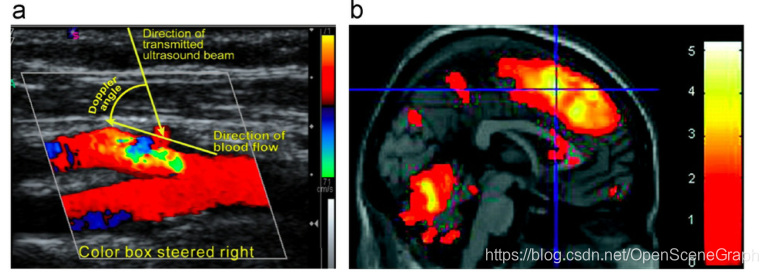

大多数CT图像是灰度渲染的,限制了可用于分割的信息量,一般不包括彩色分割方法。彩色渲染的医学图像,如彩色多普勒、功能性MRI和PET/CT[6],要么应用过于具体,要么没有被广泛采用。彩色多普勒成像[7]产生的血流图像,不同的颜色和梯度分别代表血流方向和速度。彩色多普勒血流受限,不适用于肿瘤或器官的渲染。图1a显示了彩色多普勒的截屏样本。功能核磁共振(fMRI)如图1b所示,呈现大脑的活动,用于神经学应用。神经元活动引起脑血流量、血容量和血氧合的变化。核磁共振成像是通过获取被激活和休息的大脑的图像差异来呈现的。得到的图像以伪彩色呈现,以显示特定活动和大脑功能[8]之间的相关性。一些研究表明,PET/CT图像比单独的PET或CT更有效,可以帮助更好地检测病理,特别是对缺乏经验的保健专业人员[9]。

图1所示。彩色数字医学图像数据的例子。(a)颈动脉彩色多普勒血流[10];(b)脑功能磁共振成像研究疼痛刺激对肠易激综合征[11]的影响。(为了解释图的说明中对颜色的引用,请参考本文的web版本。)